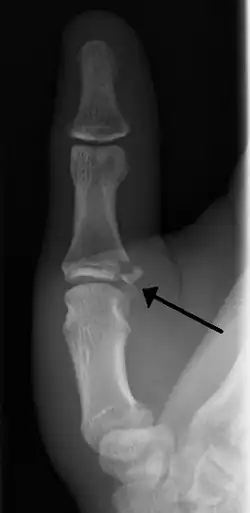

Avulsion fractures of the ulnar base of the proximal phalanx of the thumb ( Gamekeeper's fracture ) | |

- Avulsion of distal UCL causing the pulling off of a bone chip off the proximal phalanx base.[3]

When approaching this type of injury, the physician must first determine whether there is an incomplete rupture (or sprain) of the UCL, or a complete rupture. If the UCL is completely disrupted, the physician must then determine whether there is interposition of the adductor aponeurosis (Stener lesion), or simply a complete rupture of the UCL with anatomic or near-anatomic position. Radiographs are helpful in determining the possible presence of an avulsion fracture of the proximal phalanx insertion site of the ulnar collateral ligament. Stress examination, or one done under fluoroscopic guidance, can help determine the integrity of the ligament.